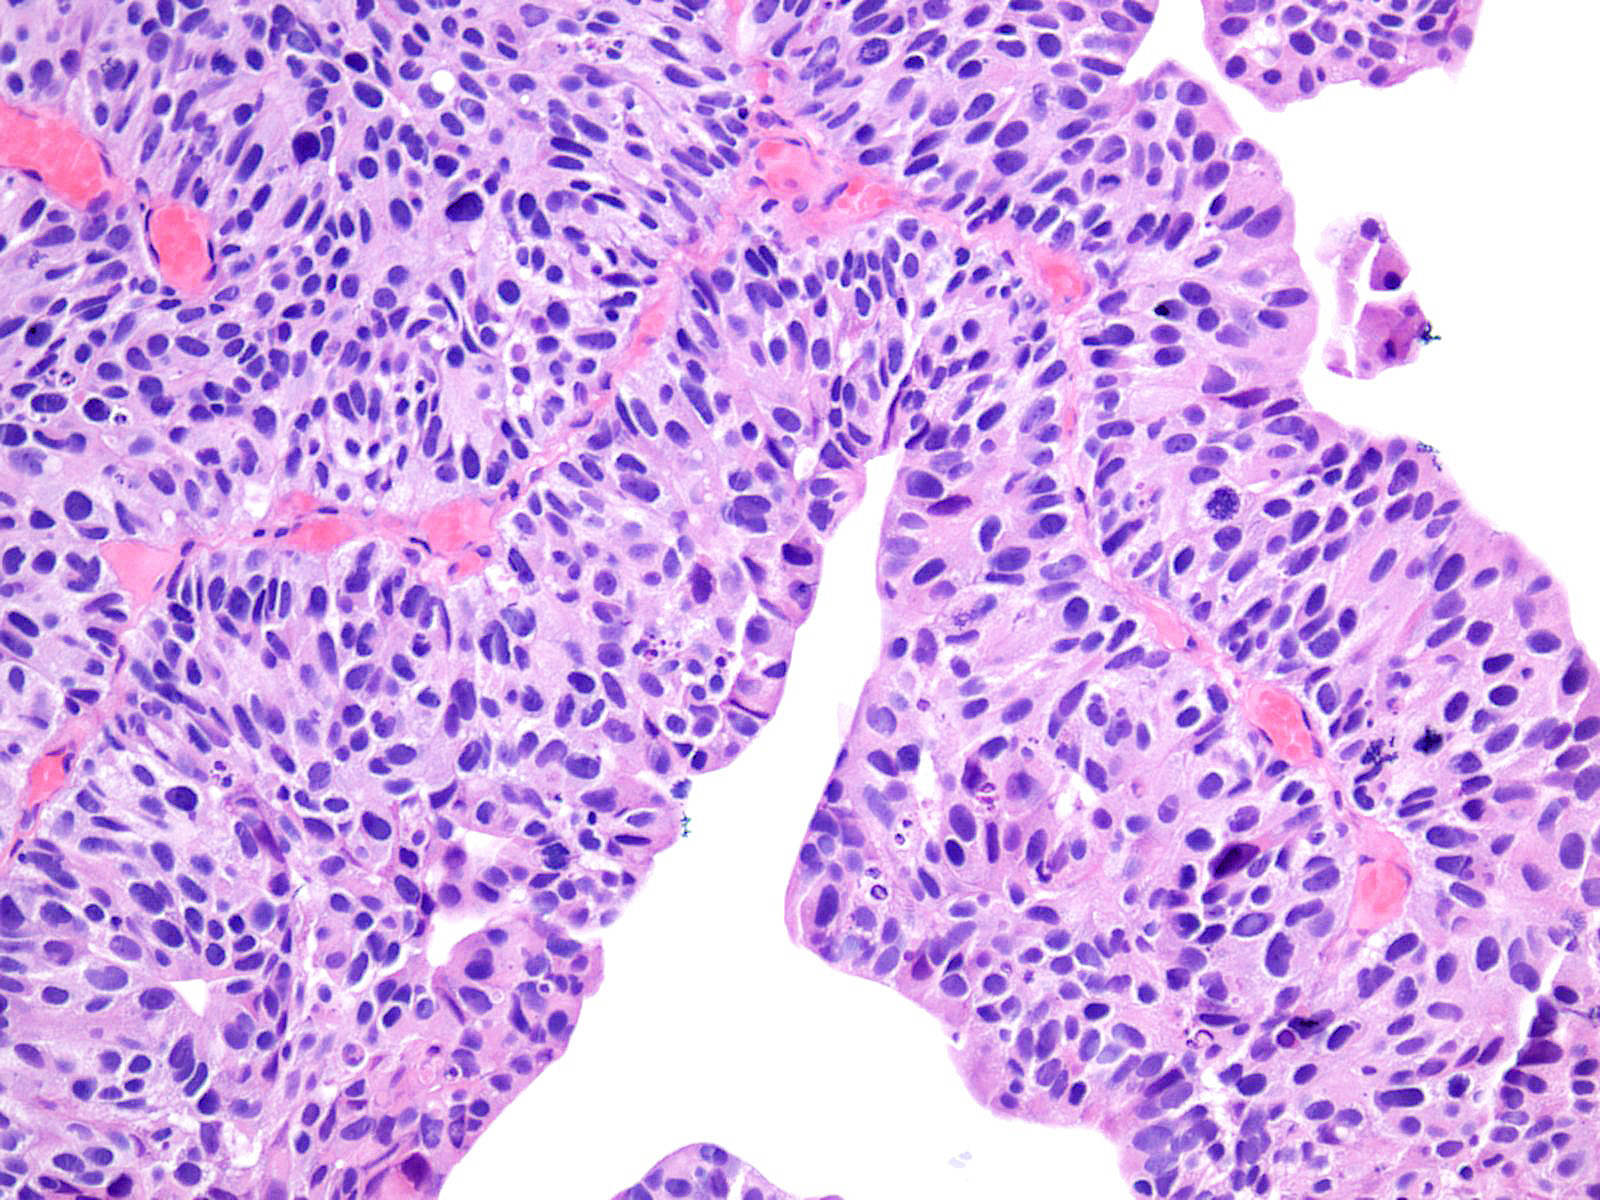

Consensus grade: High-grade papillary urothelial carcinoma (HG-PUC)

Lesion shows marked variation in nuclear size, shape and chromatin. Architecturally, cells appear irregularly clustered and the epithelium is disorganized. Mitotic figures are frequently seen at all levels.